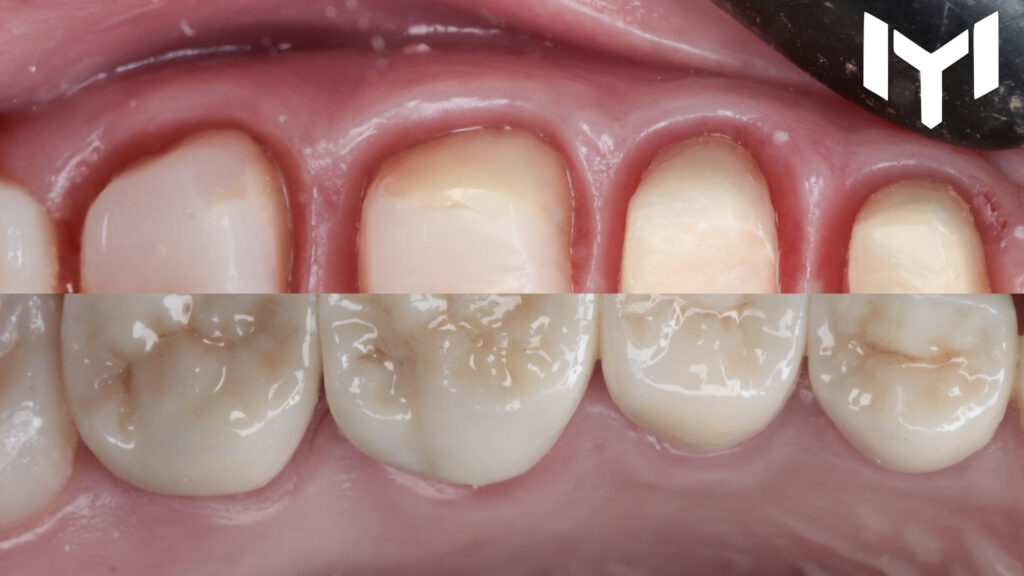

A patient presented with the need for full-coverage restorations on the upper left posterior segment (Teeth 4, 5, 6, and 7). The primary goal was to achieve biological integration and restoring function.

1- vertical preparation for the segment.

2. The Power of Temporization The “magic” happens during the healing phase. We placed high-quality provisional crowns for one month. This stage is crucial for: